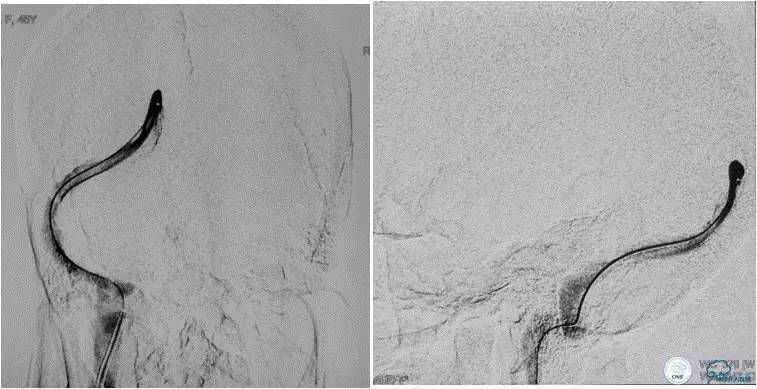

患者入院后,予以行脑动脉造影显示:右侧横窦和乙状窦交界区狭窄,左侧横窦和乙状长段重度狭窄(图3);经股静脉入路行右侧横窦和乙状窦测压显示狭窄两端压力差约为28 mmHg(图4)。遂予以阿司匹林100mg,每日一次,氯吡格雷75mg,每日一次。3d后在全麻插管下行右侧横窦-乙状窦交界处支架植入术。术中采用经右侧颈静脉入路,植入8~30mm 库克公司的ziliver支架,造影见右侧横窦-乙状窦交界处狭窄解除(图5),术中再次测压结果显示狭窄两端压力差约为1mmHg。术后自述双眼视物明显好转,但术后第3天眼底检查双视盘水肿较术前未见明显改善。

图4:经股静脉入路行右侧横窦-乙状窦狭窄处测压显示狭窄两端压力差为28mmHg。

图5:术中经右颈静脉入路植入8-30mm库克公司ziliver支架,见右横窦-乙状窦交界处狭窄明显解除,术中测压显示狭窄两端压力差约为1mmHg 。